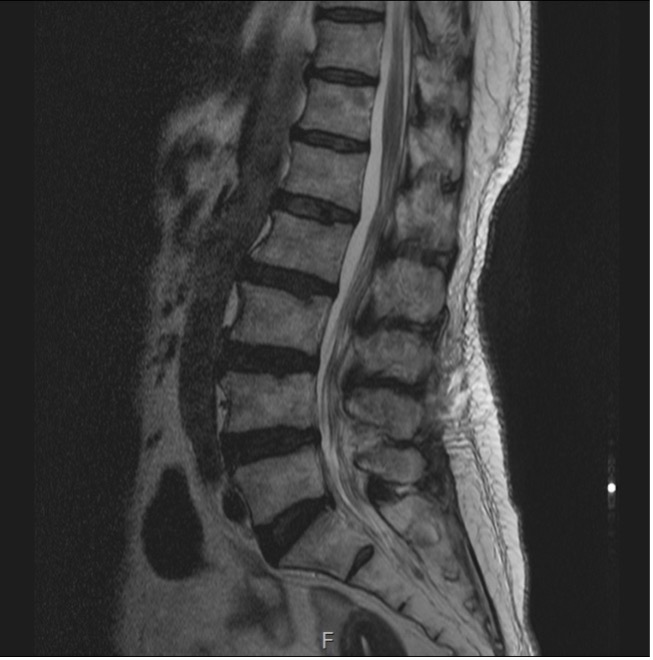

척추관협착증

척추관협착증이란

어떤 원인으로 척추 중앙의 척추관, 신경근관 또는 추간공이 좁아져 허리의 통증의 유발하거나 다리에 여러 복합적인 신경증세를 일으키는 질환

입니다.

디스크를 구성하는 수핵과 섬유륜에 퇴행성 변화가 일어나고 척추관을 구성하는 뼈와 인대 등이 두꺼워져 척추 뼈가 어긋나는 경우 척추 신경을 눌러 통증을 일으킵니다.